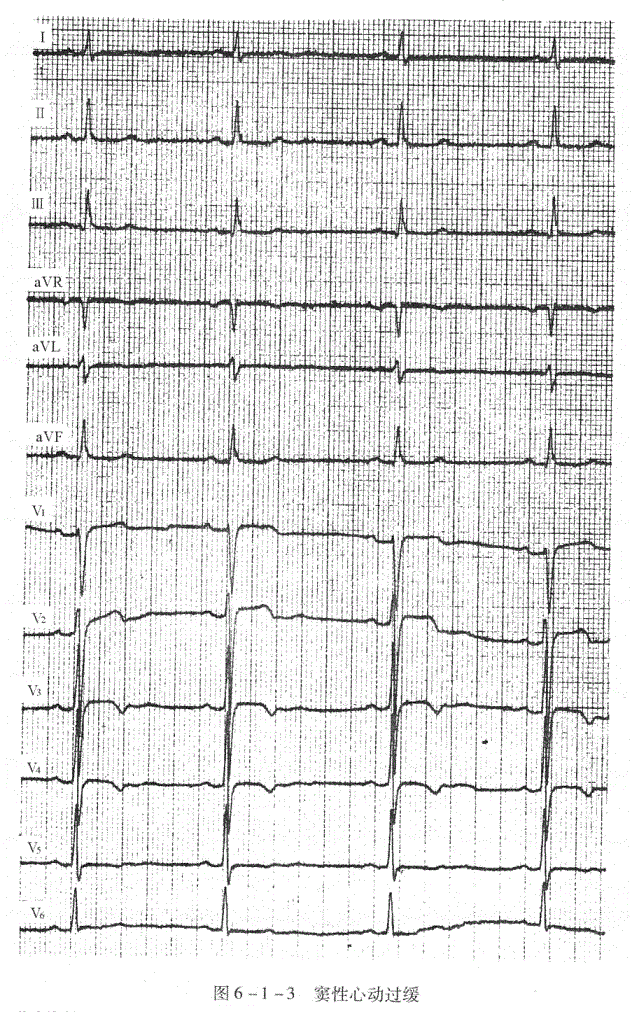

窦性P波,P波规律出现,P波在I、Ⅱ、aVF、V

导联直立,aVR导联倒置,窦性心律的频率低于60次/分(图6-1-3)。

临床资料:男性,80岁。自觉心悸,有时头晕。

心电图分析:P波符合窦性。窦性心动过缓伴心律不齐,心率48次/分,I、V

导联T波低平,V

、V

导联T波倒置,Q-T=410ms。

心电图诊断:①窦性心动过缓伴心律不齐;②T波改变。